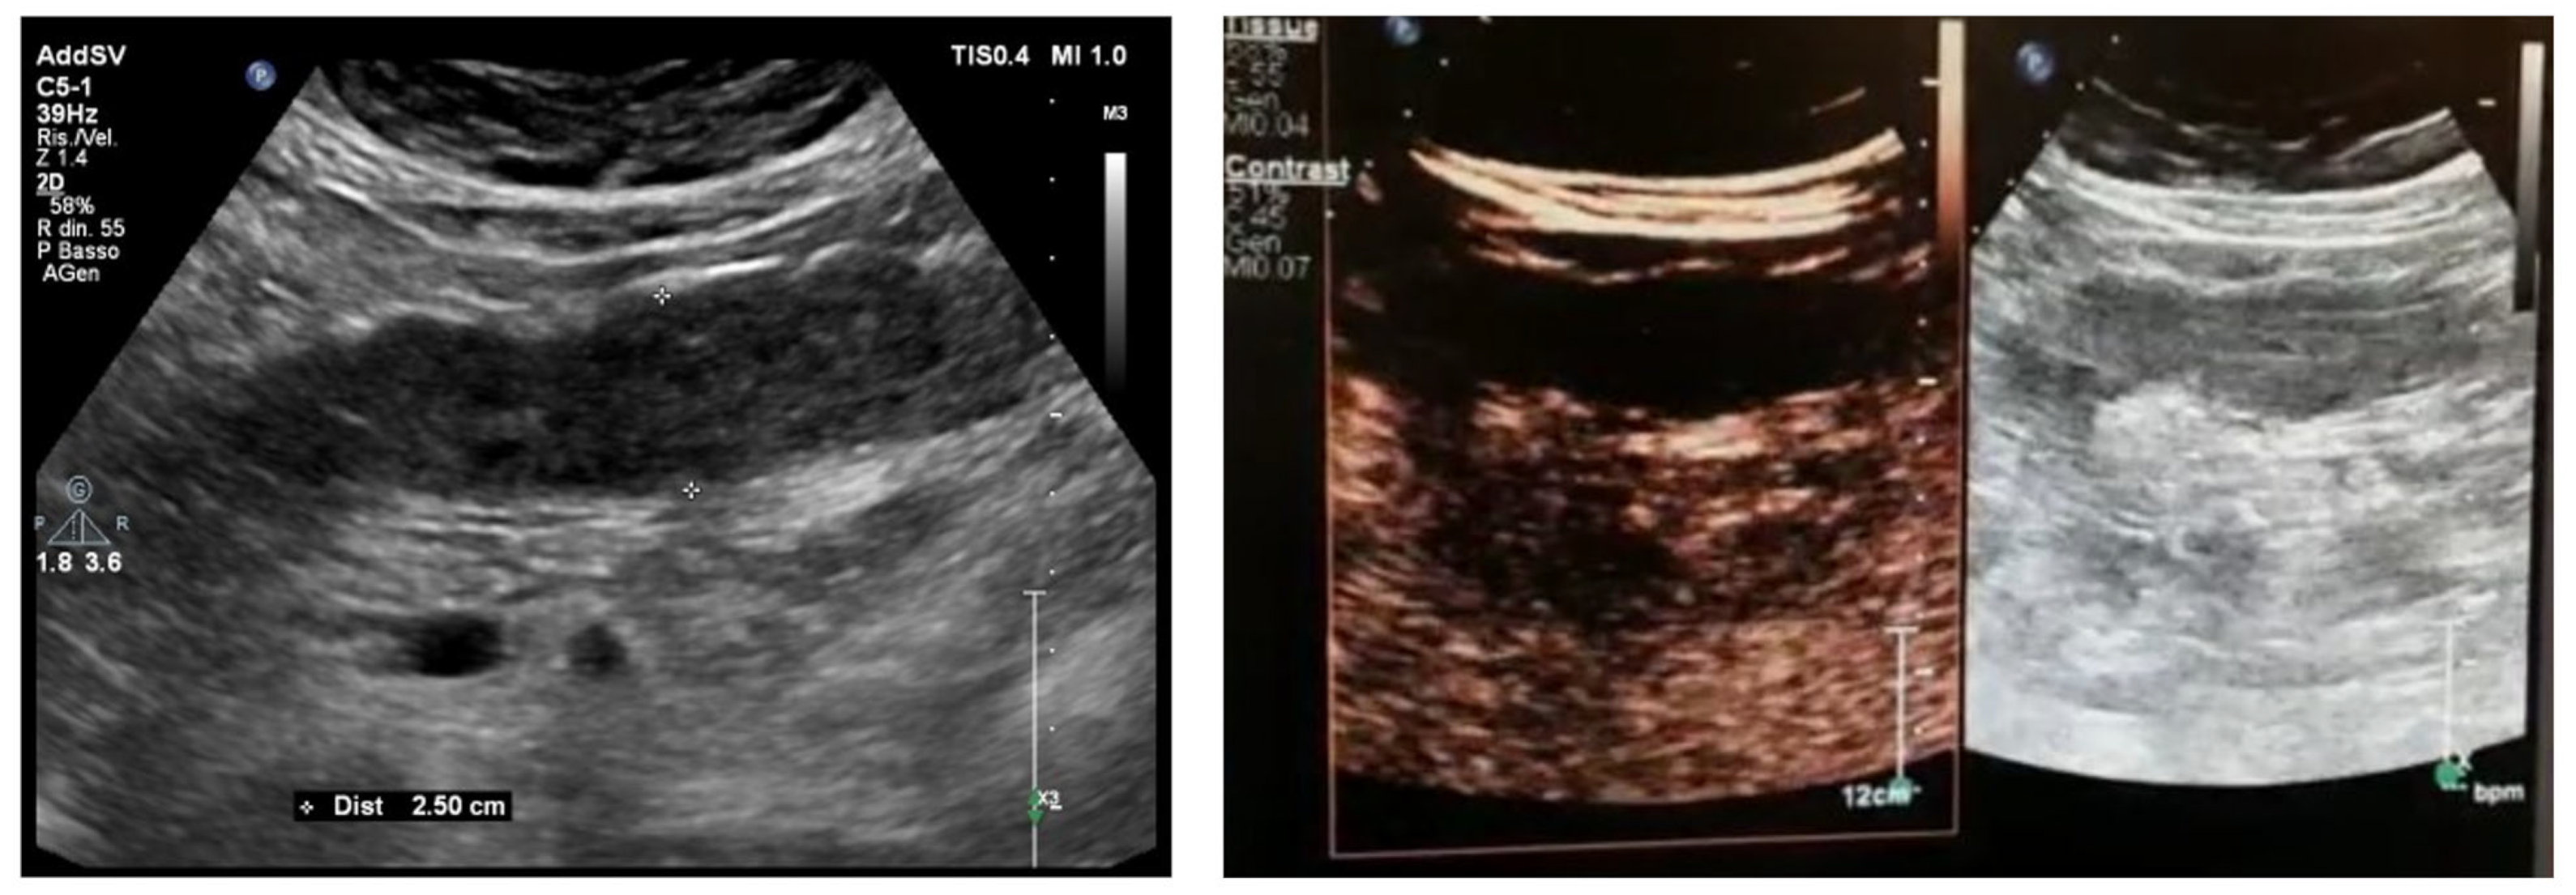

6.1. GIUS Signs of SBO

8.1. Non-Occlusive Mesenteric Ischemia

8.2. Acute Venous Mesenteric Ischemia